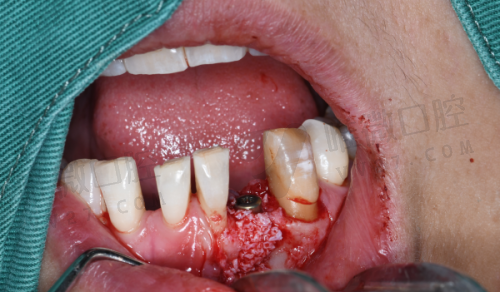

种植牙价格不同,原因可不仅仅是品牌。举个栗子,即刻种植,虽然价格高一点(8698元起),但它的“快”可是骗不了人的。当天拔牙、当天种植、当天戴冠——节省了你跑医院的次数,也降低了二次手术的风险。而穿颧种植的价格更高一些,则是因为它解决的是“骨量极度不足”的老大难问题。这种以“精细度”为王的手术,价格自然起飞。